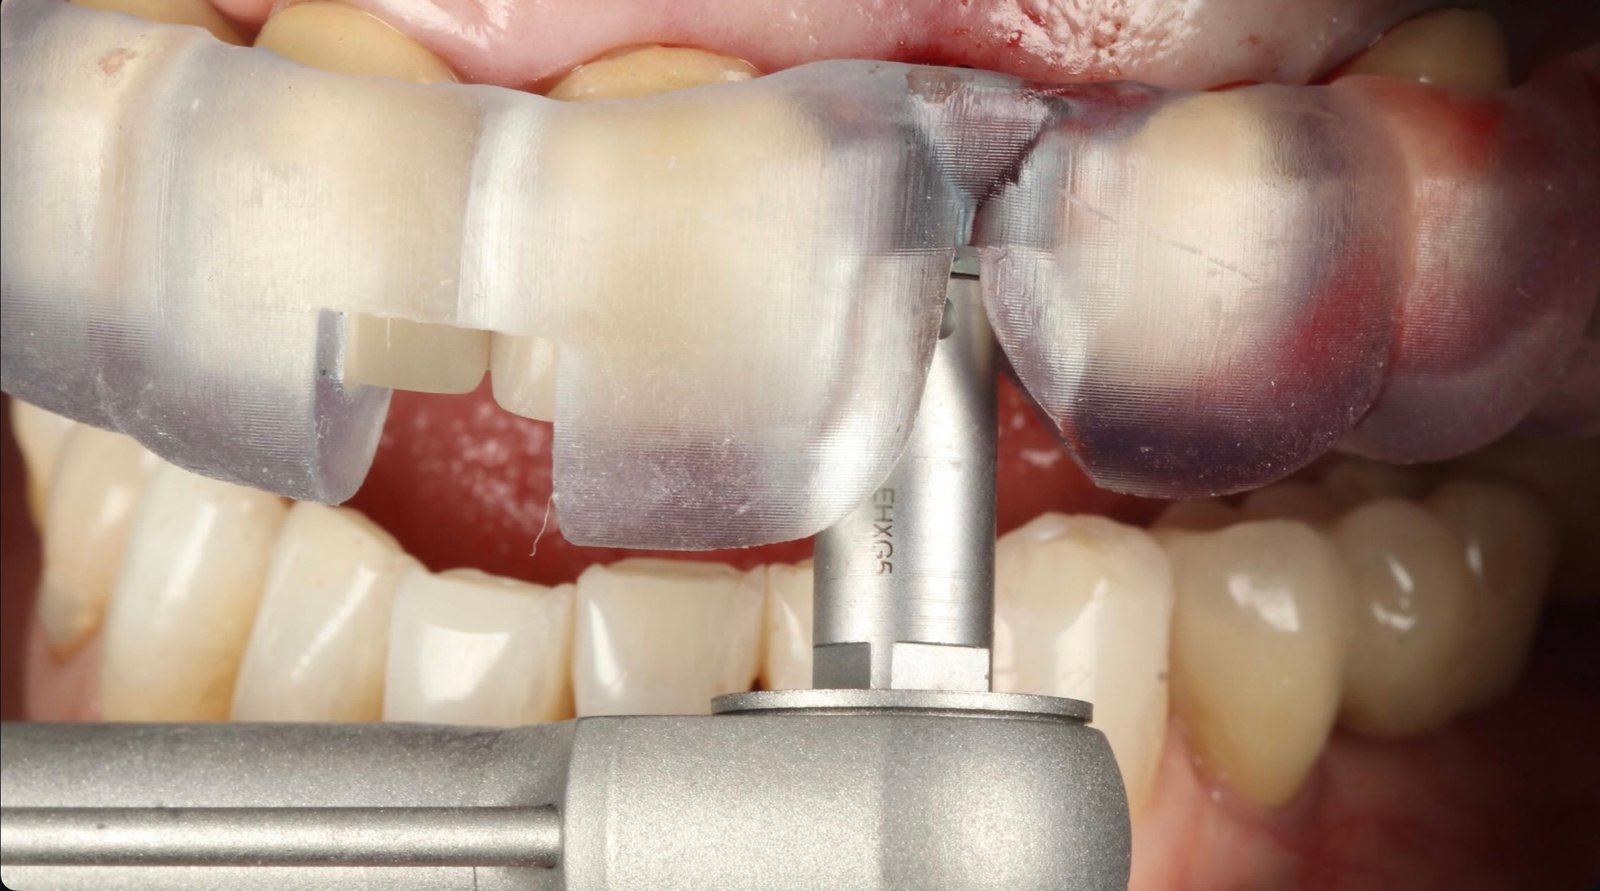

Planificamos cada caso con cirugía guiada digital para una colocación precisa y segura, reduciendo molestias y acelerando la recuperación.

2. Colocación del implante: procedimiento mínimamente invasivo con guía quirúrgica.